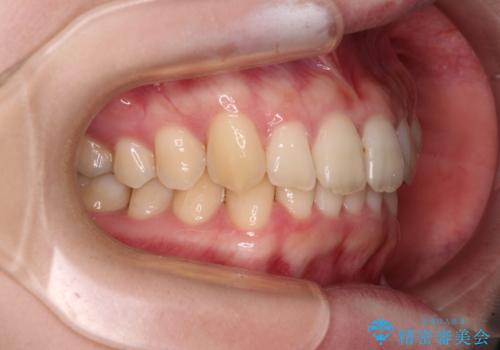

- 全体的な歯列の叢生を気にして来院された患者様です。

奥歯の咬み合わせを見ると、片方は上顎が下顎に対して相対的に前方にあり、他方は交叉した咬合の状態でした。

咬み合わせを改善するためには、上顎臼歯を後方に移動させた咬み合わせにする必要があります。

インビザライン単体で改善することも可能ですが、ディープバイトのためインビザライン単体で達成する可能性が低いと考えられたため、カリエール・ディスタライザーという補助装置を併用して、より確実性を上げることとしました。